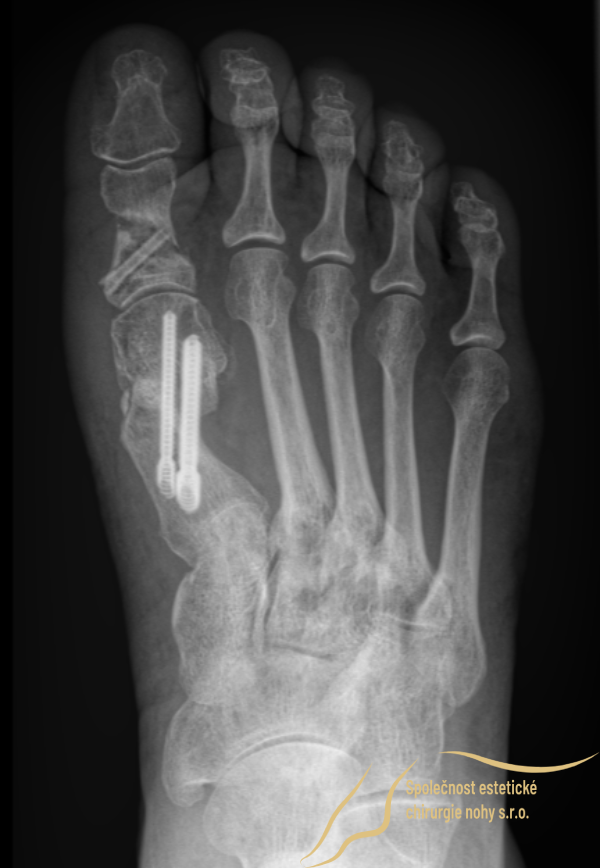

Postoperative X-Ray:

The X-ray confirms the stabilization of the corrected toe position with:

Two titanium screws in the instep.

One absorbable magnesium screw in the toe.

Note: Titanium screws remain permanently in the bone, while the magnesium screw dissolves within 1.5 years.